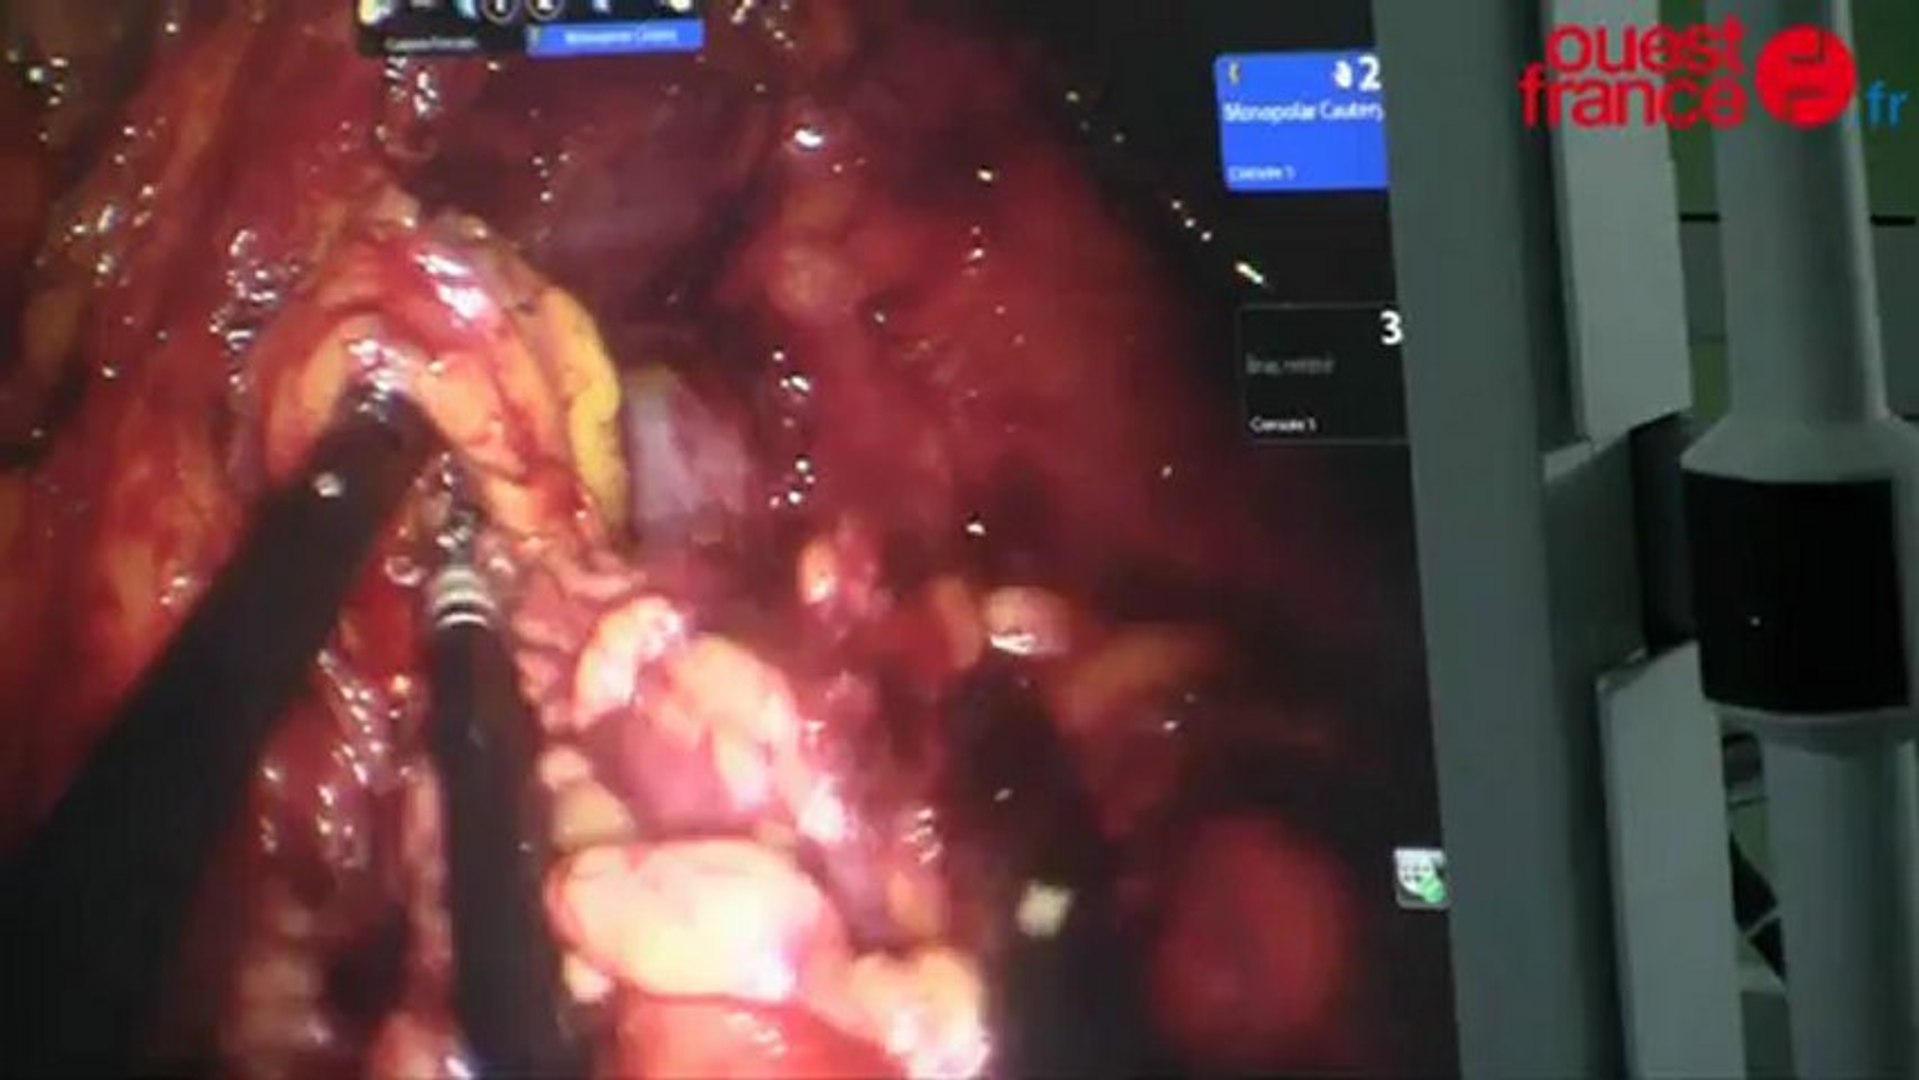

Don de rein un numéro des gens croissant choisissent de. Ablation d’un rein L’intervention s’est déroulée au centre hospitalier LyonSud, grâce à un robot et par la voie vaginale La patiente a pu rentrer chez elle le soir même Arrivée au centre hospitalier LyonSud à 7 heures du matin le 15 juillet dernier, Magali a pu rentrer chez elle peu après 19 heures avec un rein en moins. Selon l’étude, il serait possible d’éviter l’ablation d’un rein chez des patients souffrant d’un cancer métastatique SPL/BSIP La prise en charge par thérapie ciblée fait aussi bien que la chirurgie Depuis vendredi dernier, la ville de Chicago héberge plus de cancérologues du monde entier venus assister à la 54e.

Régime alimentaire après l'ablation d'un rein Dans la quasitotalité des cas, il n'y a pas de régime particulier à suivre " Après la convalescence, il faut vivre normalement, faire du sport, et surtout boire beaucoup d'eau ", conseille le spécialiste. Pas moins que celle d'avoir un organe pair Comme pour toute autre personne, l'espérance de vie est influencée par l'information héréditaire, environnement, mode de vie, accro aux mauvaises habitudes, présence. Opération d'ablation d'un rein par un robot au CHU de Rennes Les maladies du cerveau coûte 685 milliards d'euros à l'Europe par an par Gilles Edann chef du pôle de neurosciences du CHU de Rennes.

Des chirurgiens des Hospices civils de Lyon ont réalisé une première mondiale enlever un rein abîmé d’une patiente en le faisant passer non pas par une lésion abdominal, mais par le vagin. Meilleure réponse bonjour, ma mère un ablation de son sein gauche il y a 7 ans et parfois elle ressent encore des douleur a l'endroit de ses cicatrices le médecin lui dit que c'est normale, je me rapel qu'un mois après son opèration l'endroit de. Après avoir été opéré d'un cancer du rein, le suivi est essentiel "Lors de la consultation postopératoire, on présente au patient le résultat de l'analyse de la tumeur qui a été retirée, ce qui lui permet de comprendre sa pathologie.

Nephrectomie Robotisee Da Vinci Pour Traiter Le Cancer Du Rein

1ere Mondiale L Ablation D Un Rein Par Chirurgie Robotique En Ambulatoire

Une Premiere Mondiale L Ablation D Un Rein Sans Hospitalisation Le Point